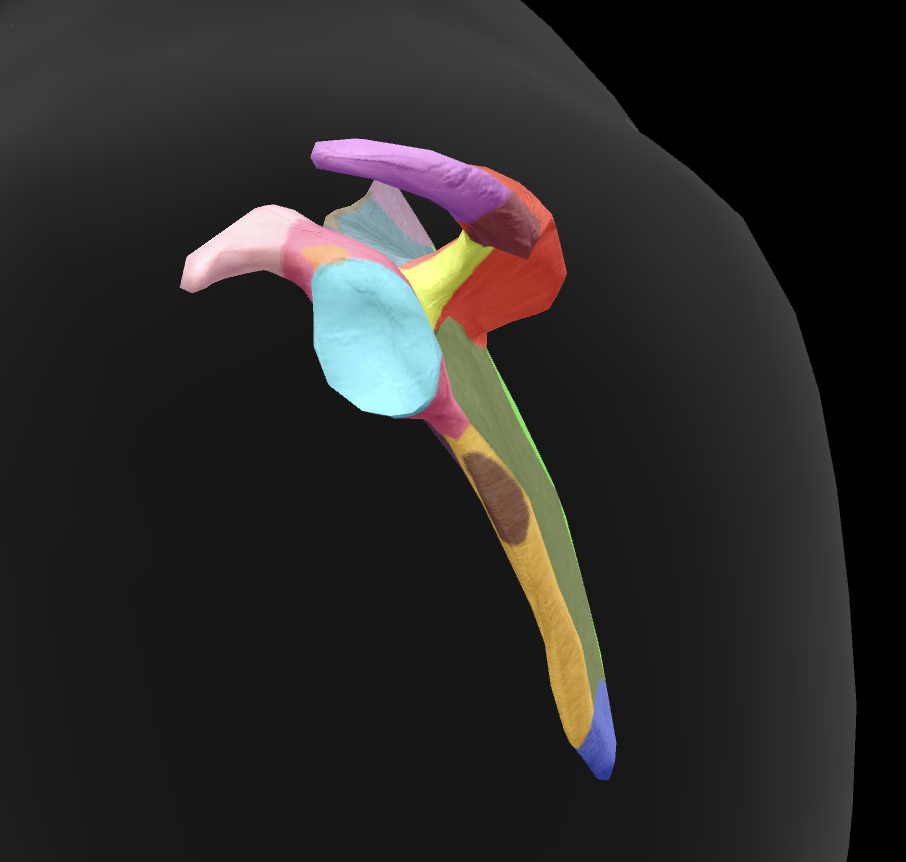

scapula

What is this boney landmark?

spine of scapula

What is this boney landmark?

supraspinous fossa

What is this boney landmark?

infraspinous fossa

What is this boney landmark?

acromion process

What is this boney landmark?

superior angle

What is this boney landmark?

inferior angle

What is this boney landmark?

lateral border

What is this boney landmark?

medial border

What is this boney landmark?

subscapular fossa

What is this boney landmark?

spinoglenoid notch

What is this boney landmark?

glenoid fossa

What is this boney landmark?

supraglenoid tubercle

What is this boney landmark?

infraglenoid tubercle

What is this boney landmark?

coracoid process

What bone is this?

humerus

What is this boney landmark?

head

What is this boney landmark?

anatomical neck

What is this boney landmark?

surgical neck

What is this boney landmark?

lesser tubercle

What is this boney landmark?

bicipital grove

What is this boney landmark?

deltoid tuberosity

What is this boney landmark?

shaft

What is this boney landmark?

capitulum

What is this boney landmark?

trochlea

What is this boney landmark?

radial fossa

What is this boney landmark?

coronoid fossa

What is this boney landmark?

medial epicondyle

What is this boney landmark?

lateral epicondyle

What is this boney landmark?

greater tubercle